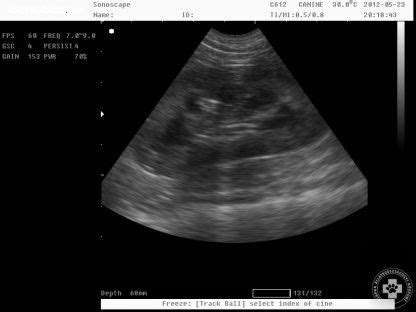

A Czeizel Intézetben a csecsemő ultrahangvizsgálatot Dr. Karádi Zoltán gyermekradiológus szakorvos, a Semmelweis Egyetem II.Szívfejlődési rendellenességgel Magyarországon évente kb. 800 gyermek születik, ám ennek csupán a negyede súlyos, mely már az első életévben megoldást igényel.

Az újszülöttek fejlődésében számos eltérés fordulhat elő, melyek közül néhány már magzati korban felismerhető, míg mások csak születés után válnak nyilvánvalóvá. A leggyakoribb feltárt fejlődési rendellenességek közé tartozik a vesemedence tágulata, melynek eredete ultrahangvizsgálattal tisztázható. A húgyúti fejlődési rendellenességek kezdetben tünetmentesek, azonban, ha a gyermek nem részesül szoros követésben és preventív kezelésben, akkor súlyos húgyúti gyulladások sorozata alakulhat ki, mely hosszú távon a vesét is veszélyezteti.